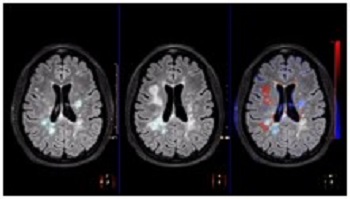

Supports the visualization of brain images for the evaluation and monitoring of changes across multiple time points. The application performs automatic registration between studies and provides semi-automatic segmentation and editing tools for volumetric measurement of brain lesions.

• The Comparative Brain Imaging feature uses bias field-correction, intensity scaling, image registration and mathematical subtraction to provide color-coded images highlighting subtle brain changes over time.